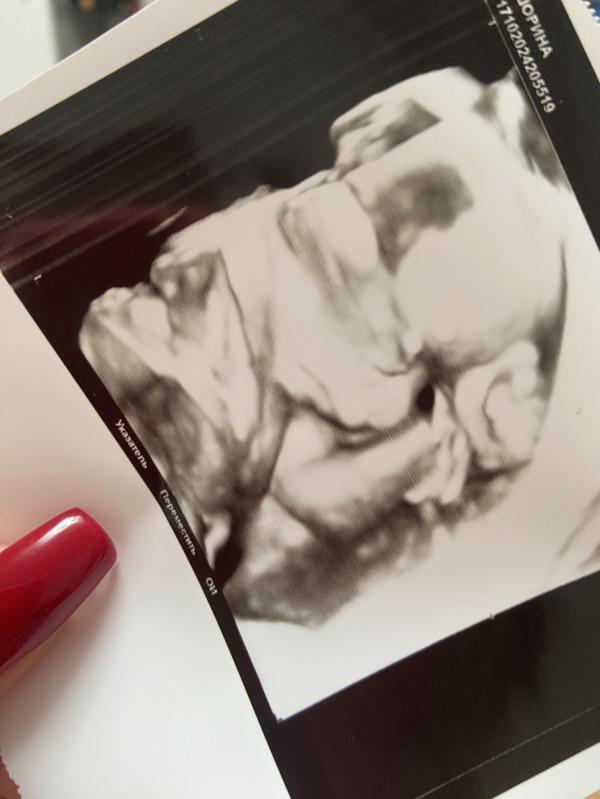

Второй скрининг пройден! Малыш здоров: вес 312гр, ЧСС, кровоток и развитие в норме - ура!

Второй скрининг пройден😻 Малыш в прекрасном состоянии! Чсс, вес, кровоток, воды, развитие - все отлично😋

Вес ~ 312гр

17.10.2024